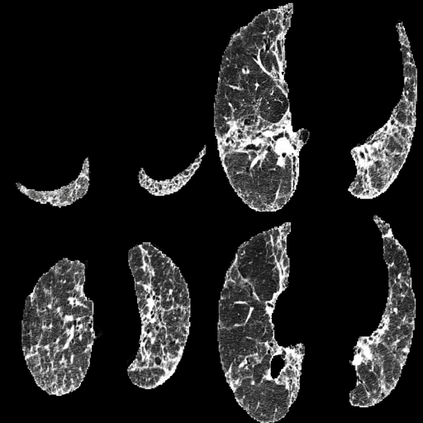

In the field of medical imaging, particularly in tasks related to early disease detection and prognosis, understanding the reasoning behind AI model predictions is imperative for assessing their reliability. Conventional explanation methods encounter challenges in identifying decisive features in medical image classifications, especially when discriminative features are subtle or not immediately evident. To address this limitation, we propose an agent model capable of generating counterfactual images that prompt different decisions when plugged into a black box model. By employing this agent model, we can uncover influential image patterns that impact the black model's final predictions. Through our methodology, we efficiently identify features that influence decisions of the deep black box. We validated our approach in the rigorous domain of medical prognosis tasks, showcasing its efficacy and potential to enhance the reliability of deep learning models in medical image classification compared to existing interpretation methods. The code will be publicly available at https://github.com/ayanglab/DiffExplainer.